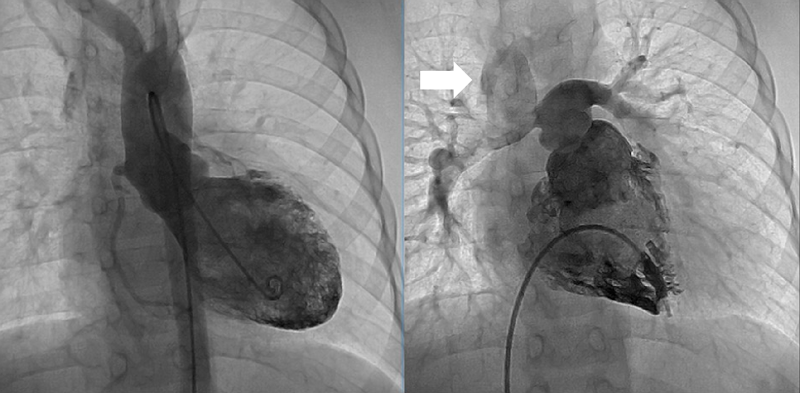

Two years after the operation, the diameter of the TV annulus was found to be 10.8 mm (Z-score: −2.73), and bidirectional flow through ASD was observed on echocardiography. Computed tomography showed that the systemic-to-pulmonary shunt had been occluded, suggesting increased antegrade pulmonary blood flow from the RV. Cardiac catheterization showed a mean PA pressure of 13 mmHg. At the age of 3 years and 6 months, 1.5VR was performed, consisting of the bidirectional Glenn anastomosis, ASD closure, and division of the systemic-to-pulmonary shunt already occluded. The diameter of the TV annulus was measured intraoperatively as 13 mm (Z-score: −2.03). Cardiopulmonary bypass time and cross-clamp time were 174 min and 22 min, respectively. Angiography at 1 year postoperatively showed adequate development of the PAs and unobstructed left ventricular outflow tract (Fig. 2). The SVC and right atrial pressures were 13 mmHg and 6 mmHg, respectively. Thirteen years after the operation, the patient is in a good general condition with normal sinus rhythm. The latest investigation on echocardiography illustrated no sign of right heart failure, such as dilatation of the inferior vena cava, a reversal flow in the inferior vena cava, and right ventricular systolic dysfunction. The TV diameter was 25.3 mm with balanced left and right ventricular cavities (Fig. 3). Table 1 summarizes consecutive changes in the TV diameter, a TV-to-mitral valve diameter ratio, mean PA pressure, and RV end-diastolic pressure. During the course, the patient did not show significant RV diastolic or systolic dysfunction. The TV diameter and RV function did not correlate to each other.

Fig. 2 Left and right ventriculography 1 year after the one and a half ventricular repair

The left ventricular outflow tract has no significant stenosis. The pulmonary arteries are well developed. White arrow indicates the bidirectional Glenn anastomosis.